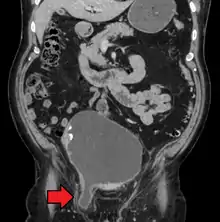

A frontal view of an incarcerated inguinal hernia (on the patient's left side) with dilated loops of bowel above.

An inguinal hernia which contains part of the bladder. Bladder cancer also present.

There are two types of inguinal hernia, direct and indirect, which are defined by their relationship to the inferior epigastric vessels. Direct inguinal hernias occur medial to the inferior epigastric vessels when abdominal contents herniate through a weak spot in the fascia of the posterior wall of the inguinal canal, which is formed by the transversalis fascia. Indirect inguinal hernias occur when abdominal contents protrude through the deep inguinal ring, lateral to the inferior epigastric vessels; this may be caused by failure of embryonic closure of the processus vaginalis.